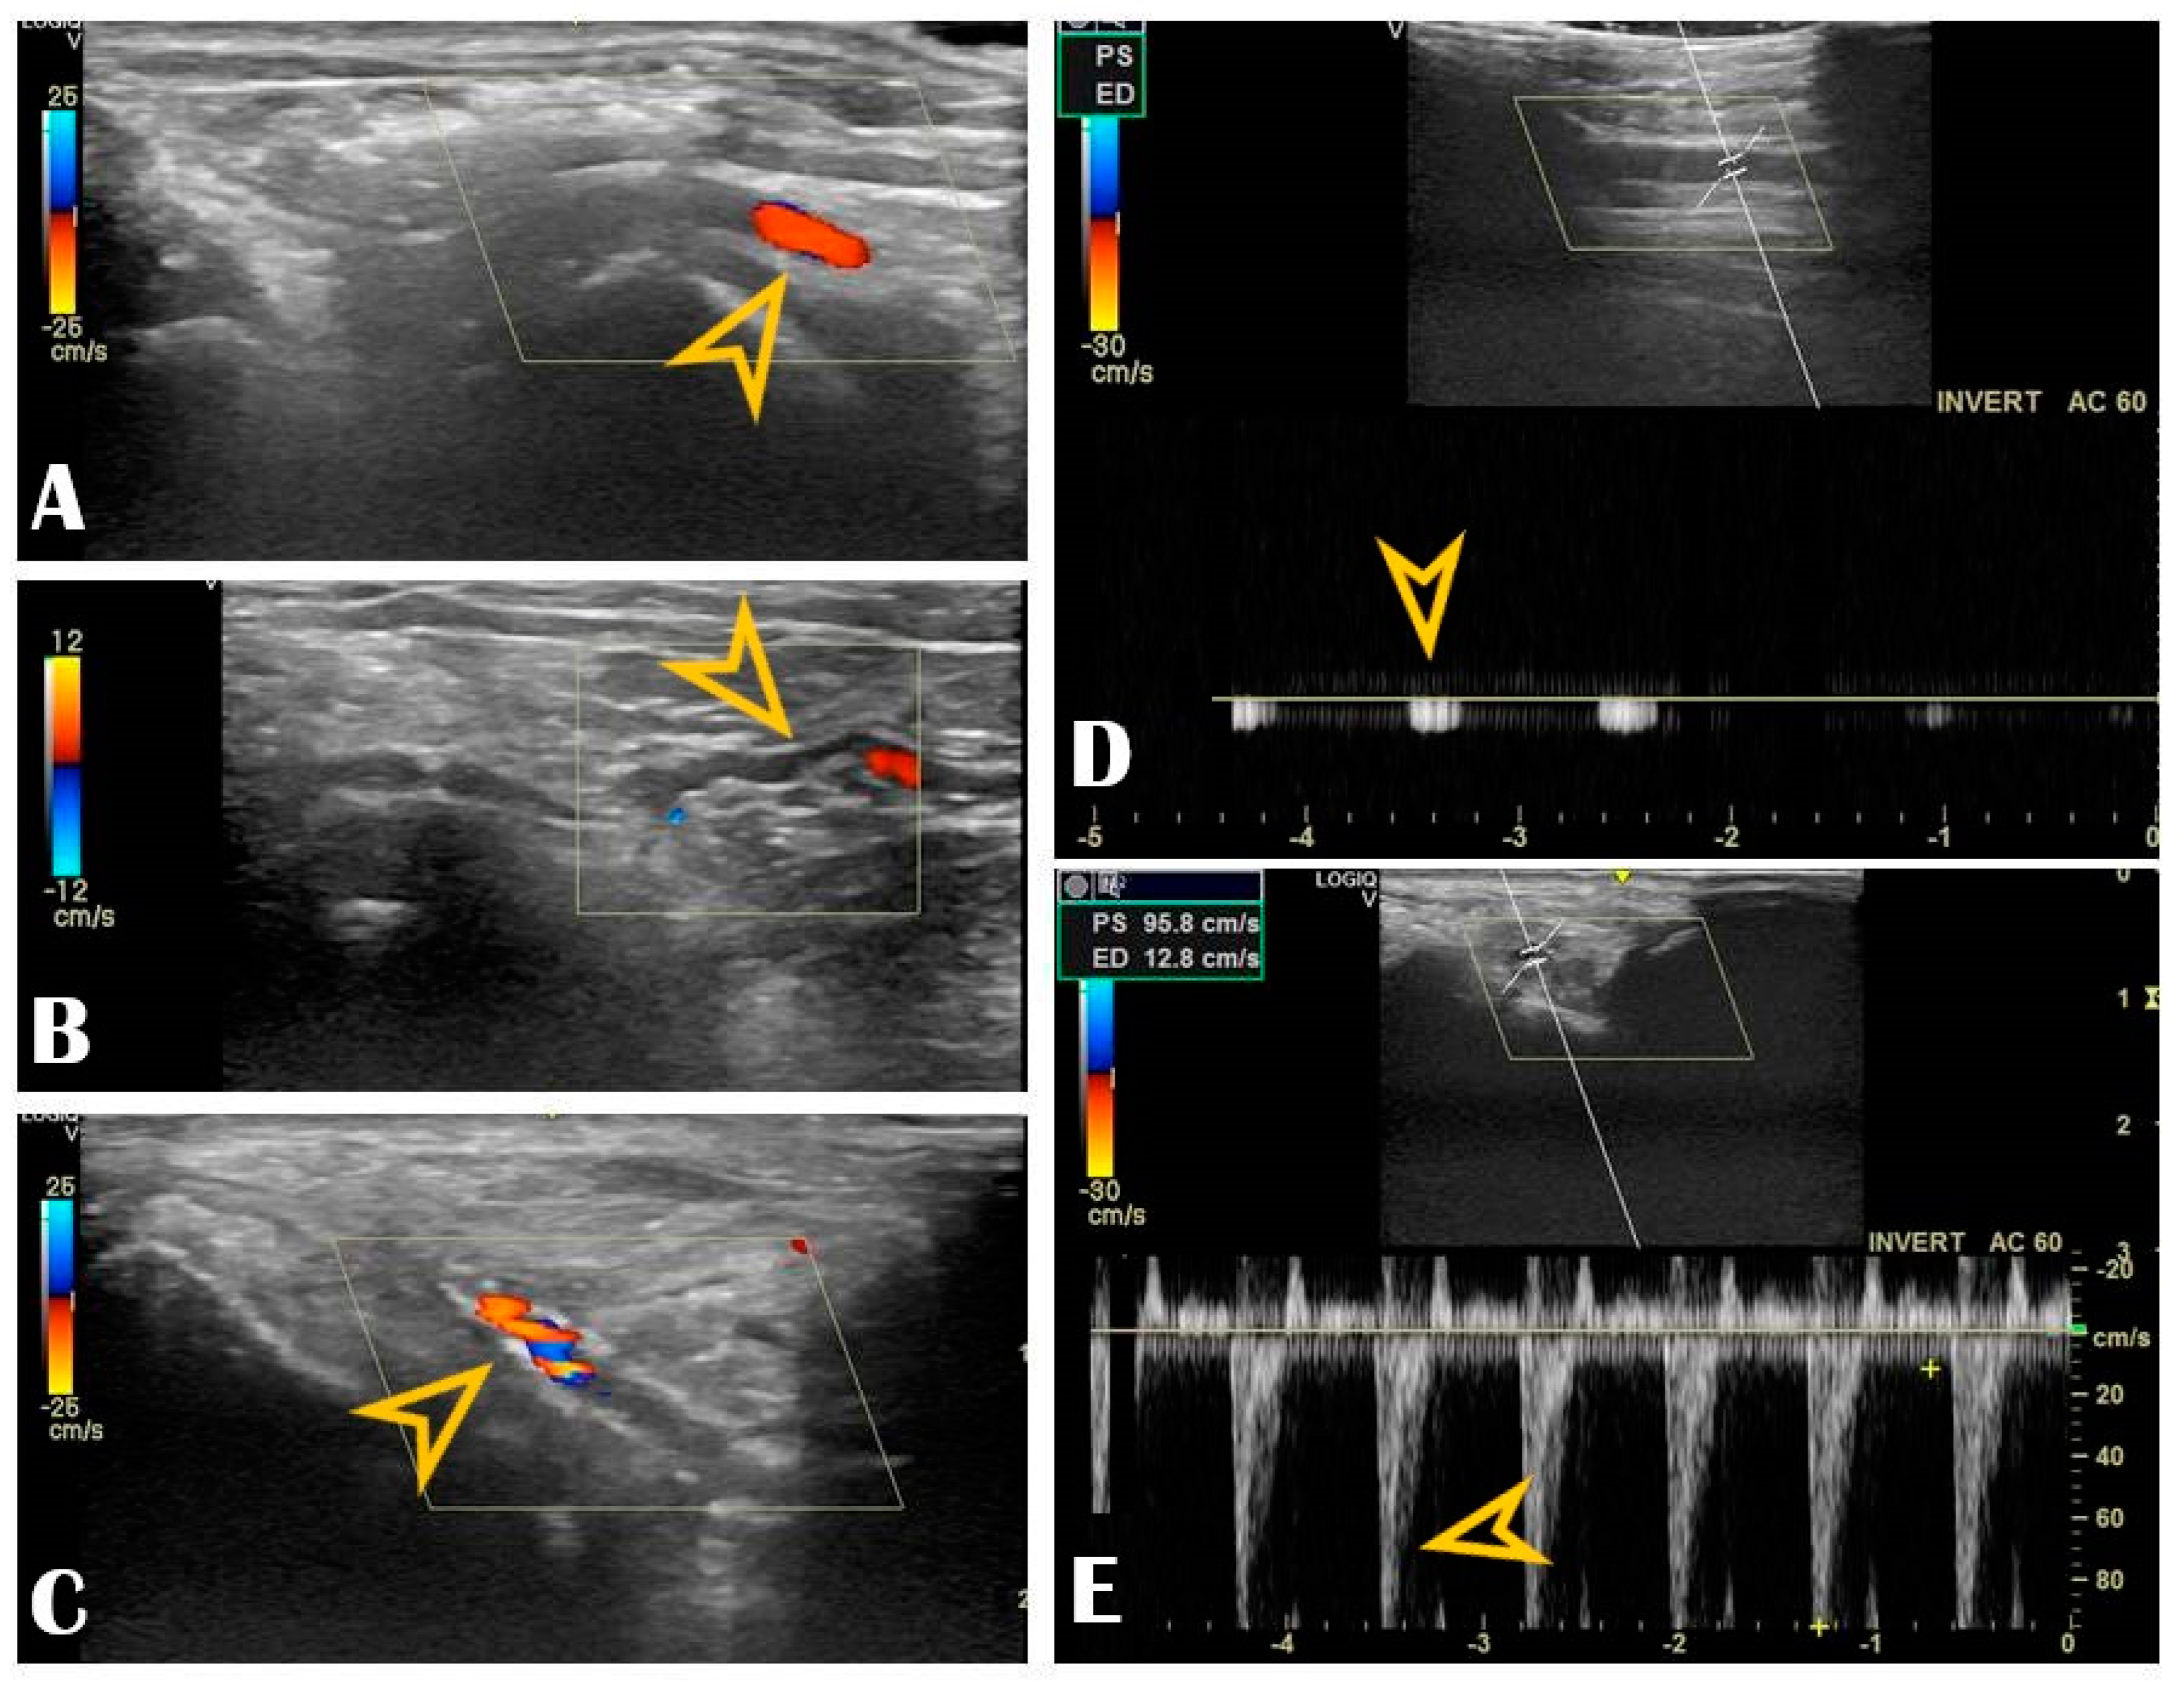

Figure 3.

Radial vascular ultrasound findings: Panel (A): Normal radial artery (arrow). Panel (B): Radial artery tortuosity (arrow). Panel (C): Radial artery calcification (arrow). Panel (D): Occluded radial artery (the arrow shows the monophasic curve and the decreased peak systolic velocity). Panel (E): Radial artery stenosis (the arrow shows the increased peak systolic velocity).